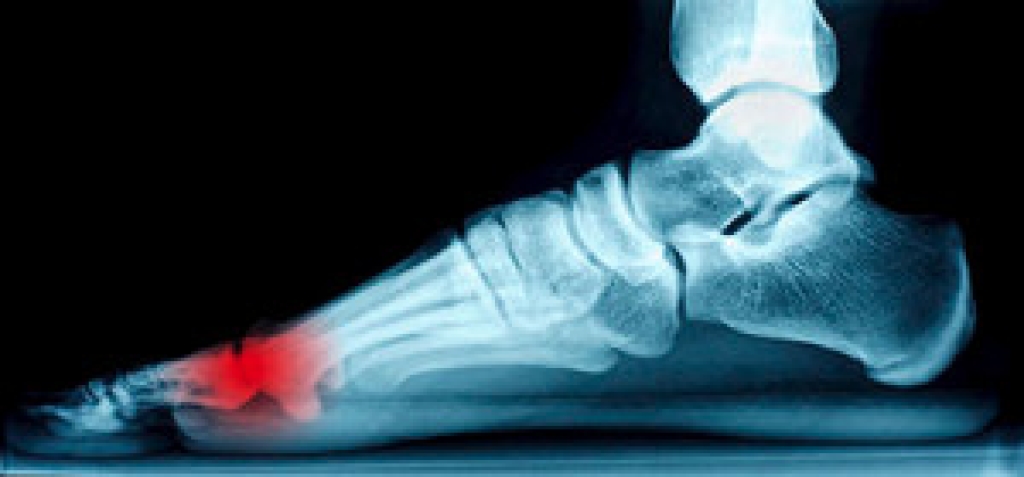

Foot Blisters

Foot blisters are often the result of friction. This happens due to the constant rubbing from shoes, which can lead to pain.

What Are Foot Blisters?

A foot blister is a small fluid-filled pocket that forms on the upper-most layer of the skin. Blisters are filled with clear fluid and can lead to blood drainage or pus if the area becomes infected.